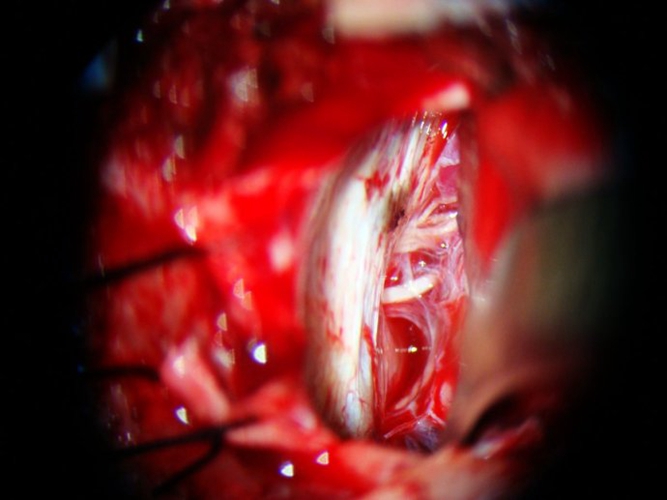

治療原發性三叉神經痛病例

血管減壓治療三叉神經痛